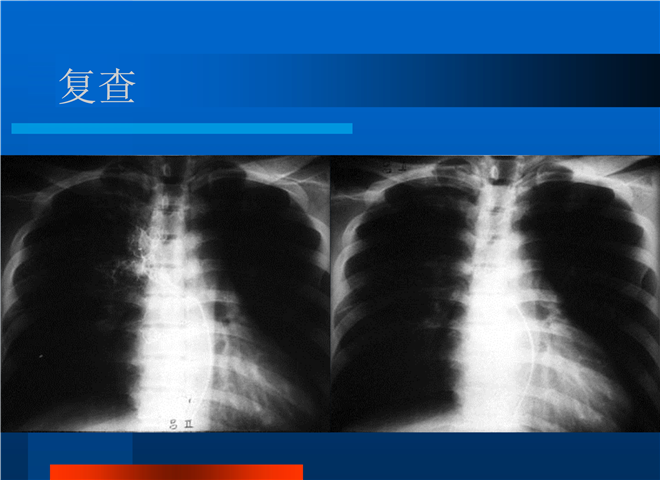

04_肺癌的介入治疗